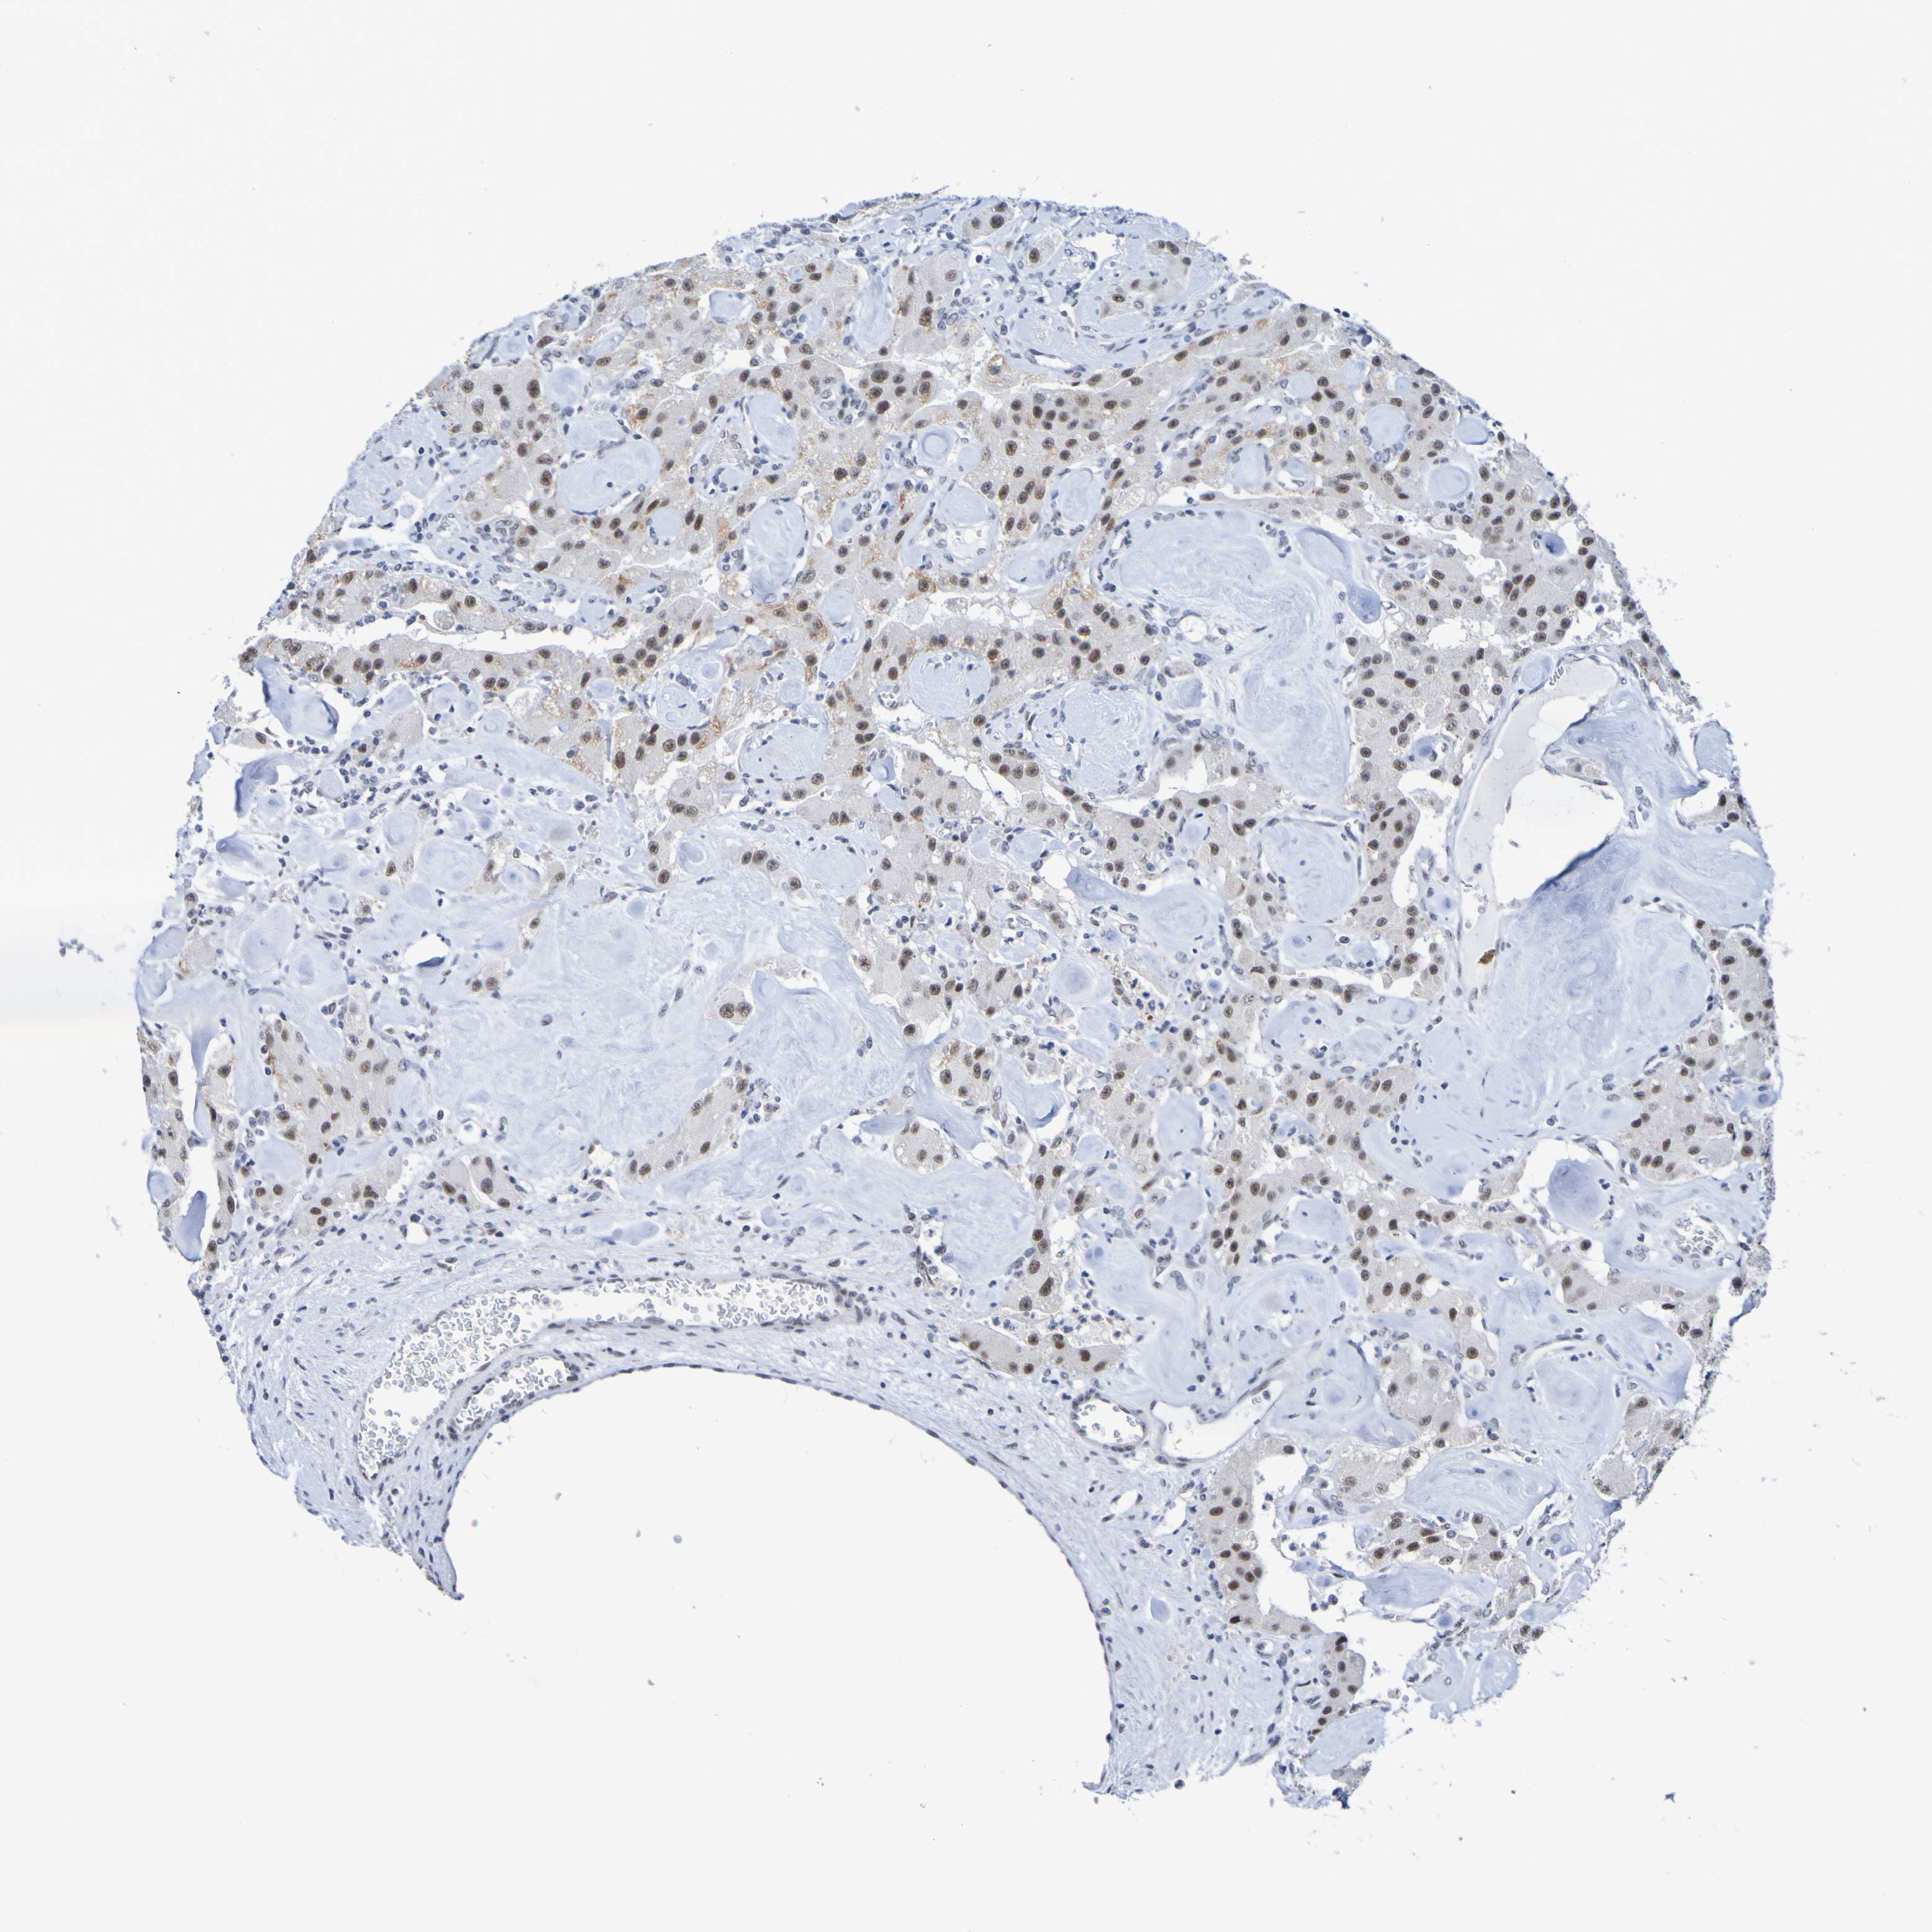

CARCINOID - Protein expressioni

A mouse-over function shows sample information and annotation data. Click on an image to view it in a full screen mode. Samples can be filtered based on level of antibody staining by selecting one or several of the following categories: high, medium, low and not detected. The assay and annotation is described here.

Each image is clickable and will lead to virtual microscopy that enables deeper exploration of all samples and also displays staining intensity scores, fraction scores and subcellular localization as well as patient and tissue information for each sample.

Antibody HPA011361

Staining

High

Medium

Low

Not detected

Intensity

Strong

Moderate

Weak

Negative

Quantity

>75%

75%-25%

<25%

None

Location

Nuclear

Cytoplasmic/membranous

Cytoplasmic/membranous,nuclear

Carcinoid, malignant, NOS